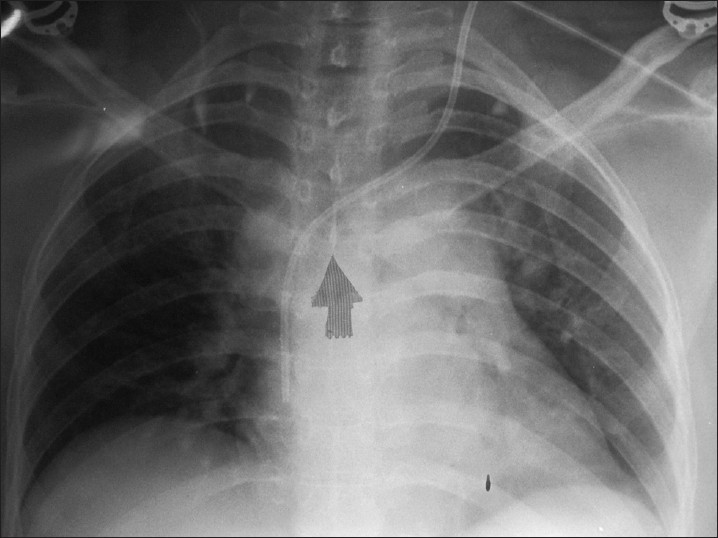

다년간에 걸친 다양한 치료들과 합병증으로 나는 고통에 어느 정도 익숙해졌다. 몇 년 전에 부분마취로 중심정맥관 삽입술을 했었다. 고용량의 항암제를 투입하면 일반 혈관이 녹아내리니까 심장 쪽 혈관에 직접 바늘을 연결해서 투입해야 한다나.

수술대에 누워 있으니 인턴이 와서 녹색 천으로 눈을 가렸다. 수술이 시작되고 나는 고개를 왼쪽으로 돌렸었는데 천을 완벽하게 가리지 않아서 내 몸을 실시간으로 찍고 있는 엑스레이가 보였다. 내 몸 안에서 움직이는 것이 느껴지는 튜브를 몸 안이 보이는 모니터를 통해서 지켜보는 건 꽤나 그로테스크하다.

JAnaesthClinPharmacol_2013_29_3_397_117114_u6.jpg 대충 이런 느낌의 모니터였다.